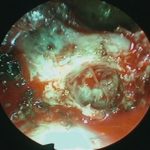

No.’25_102  摘出 中